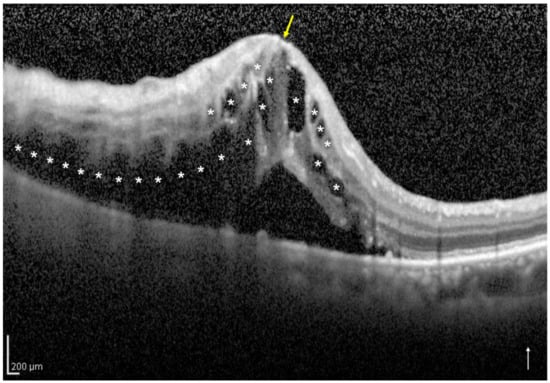

2.3. Definition and Classification of the Two Groups Using Optical Coherence Tomography

| No. of eyes with one-side IRF/both-sides IRF | 33/17 | |

| No. of eyes with foveal EZ band disruption (%) | 1 (3.0) | 8 (47.1) | <0.001 |

| No. of eyes with decimal BCVA of ≧0.5 (%) | 33 (100) | 12 (70.6) | 0.003 |